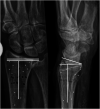

Purpose: To quantify accuracy of two radiographic measurements: dorsal/volar tilt and fracture compression, measured indirectly as ulnar variance (UV), using radiostereometric analyses (RSA) as reference standard.

Material and methods: Twenty-one fresh frozen non-fractured human cadaveric forearms (right = 11, left = 10) were thawed and eligible for inclusion. The forearms were mounted on a custom made platform that allowed for controlled forearm rotation, and they underwent two rounds of imaging (both rounds consisted of RSA and radiographs). In round one, the non-fractured forearms were radiographed. In round two, artificial DRF´s with compression and dorsal angulation were created and imaging procedures repeated. Change in tilt and UV between the non-fractured and later fractured forearms was defined as fracture-induced deformity. Deformity was measured radiographically and additionally calculated using RSA. Bland Altman analyses were used to estimate agreement between radiographically measured, and RSA calculated, fracture-induced deformity.

Results: Our results indicated that radiographs underestimate the amount of fracture-induced deformity. Mean measured differences (bias) in dorsal tilt deformity between radiographs and RSA were -2.5° for both observers. The corresponding values for UV were -1.4 mm and -1.5 mm.